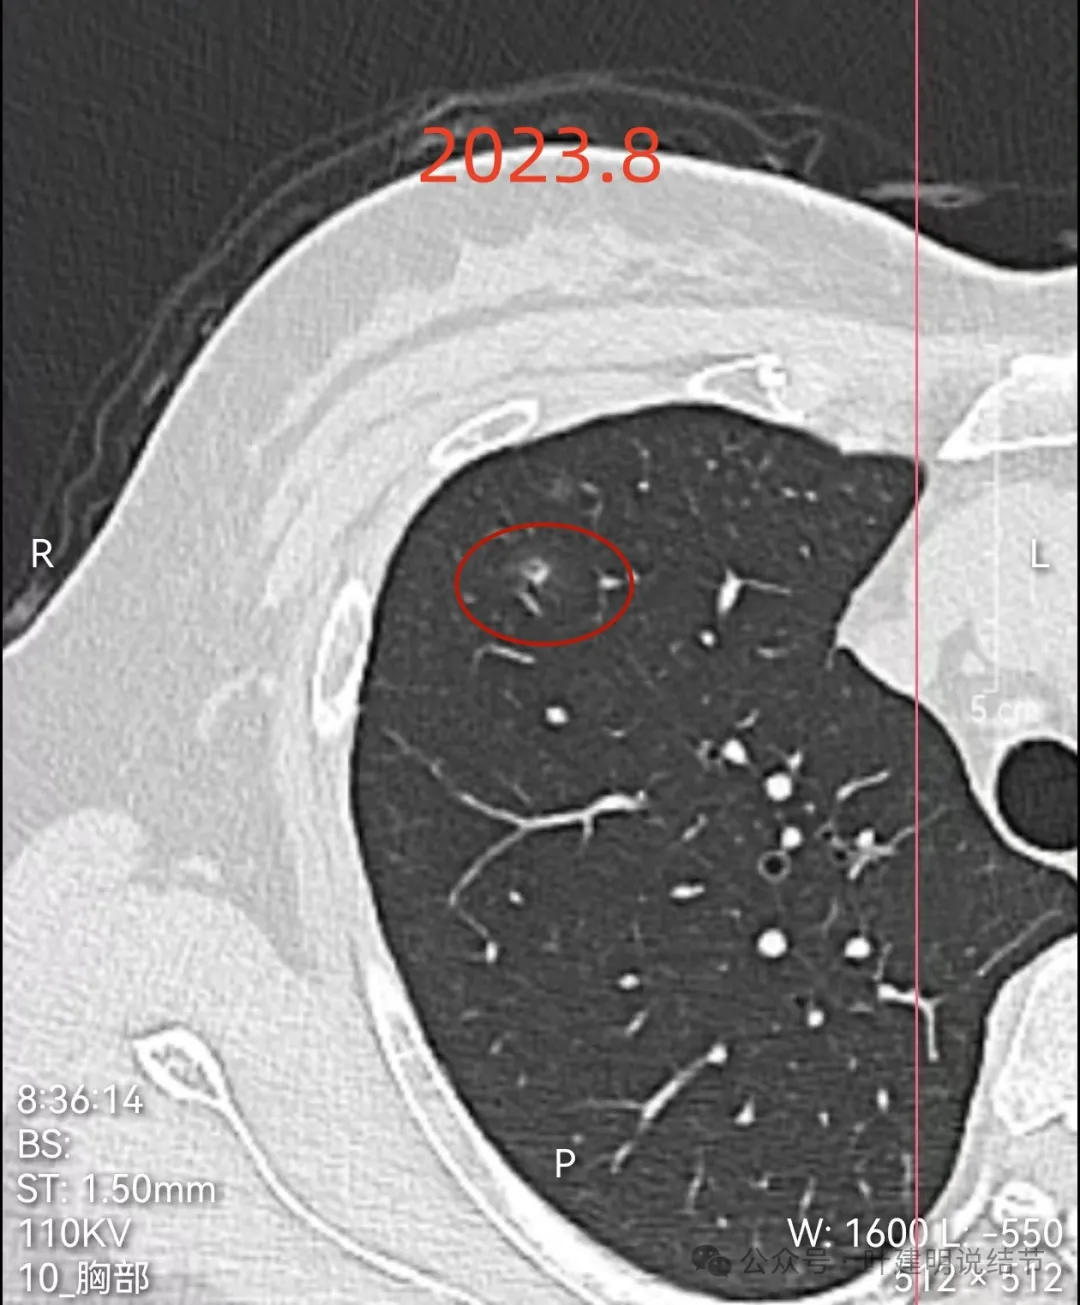

左上叶微小磨玻璃结节,轮廓较清,密度较淡,没有实性成分,考虑肺泡上皮增生或不典型增生可能性大,近期风险小,能随访。

右上叶混合密度结节,此灶周围有晕(很淡而边界欠清的磨玻璃),中间有小空泡征,空泡的壁又是实性密度的,空泡内壁圆而较光滑,邻近有小血管走过。

2023年8月时主病灶的样子,与2024年的几乎没有变化。